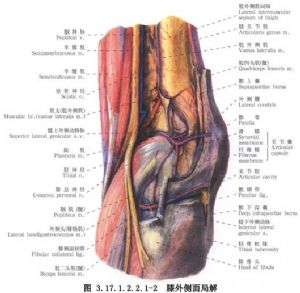

新鮮膝外側副韌帶修補術用於外側副韌帶損傷的手術治療。外側副韌帶對膝關節的穩定沒有內側副韌帶那麼重要,其損傷也較少見,原因是在屈曲位時外側副韌帶鬆弛,不致因旋轉應力受傷,伸膝位時又爲髂脛束、股二頭肌腱、外側關節囊、交叉韌帶所加強,也受到對側肢體保護免受內收位損傷。僅在膝關節輕度屈曲時關節承受內翻應力,可損傷其外側結構,包括髂脛束、外側副韌帶、外側關節囊、膕肌腱、交叉韌帶、股二頭肌、腓腸肌外側頭、腓總神經等(圖3.17.1.2.2.1-0-1~3.17.1.2.2.1-0-3)。

手術相關解剖見下圖(圖3.17.1.2.2.1-1,3.17.1.2.2.1-2)。